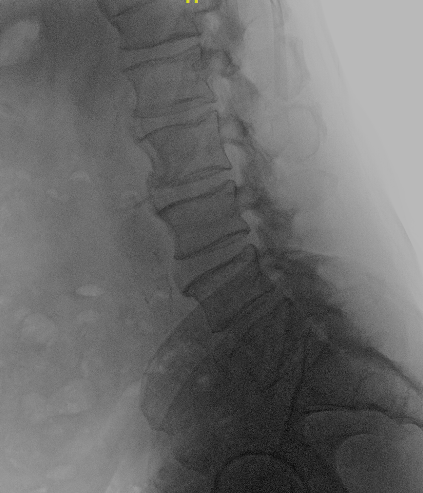

Paciente de 63 años con clínica de claudicación de la marcha.

Preoperatorio

En esta técnica hay que respetar la anatomía para no provocar una inestabilidad secundaria.